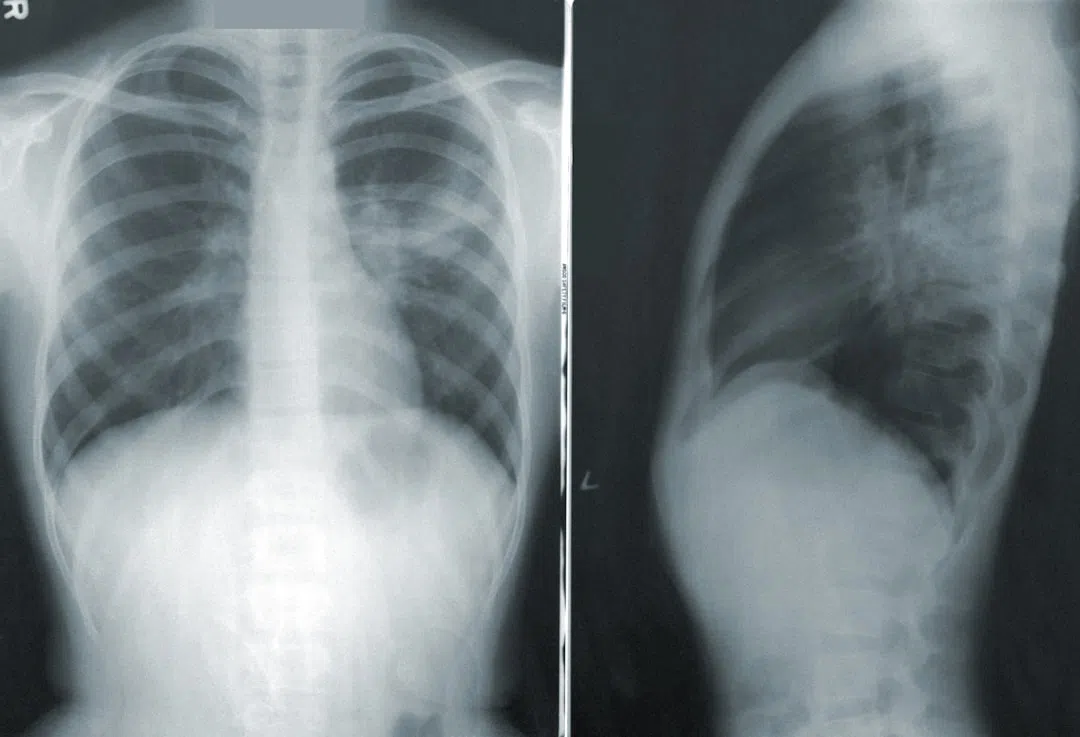

우선, 간암의 조기 발견과 관련된 기술들은 매우 진보하였습니다. 초음파, CT 스캔, MRI 등 다양한 영상 진단 기술은 간암의 초기 증상을 더욱 정밀하게 포착할 수 있도록 도와주었습니다. 이러한 진단 기술을 활용하면 환자의 상태에 맞춰 최적의 치료 계획을 세울 수 있어, 치료 성공률 역시 크게 향상되고 있습니다.